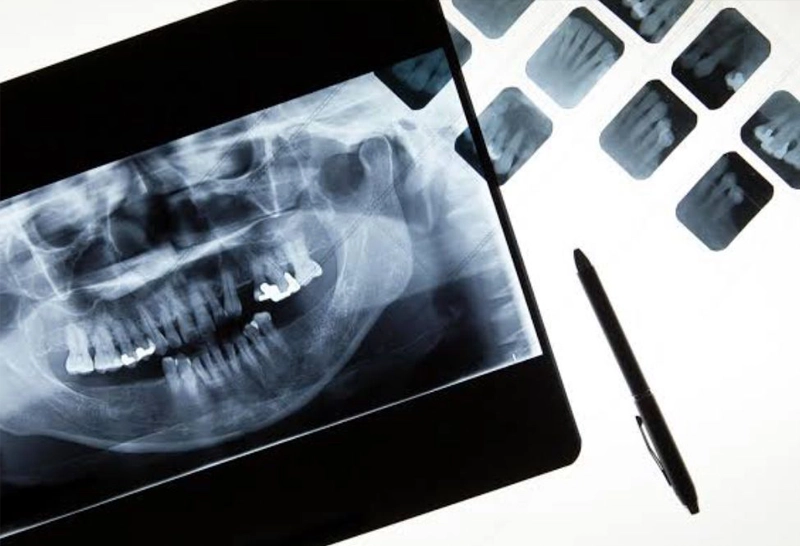

Aulas expositivas dinâmicas com vasto material ilustrativo (imagens radiológicas, tomográficas, ressonâncias, ultrassonografias, gráficos de exames laboratoriais, lâminas histopatológicas).